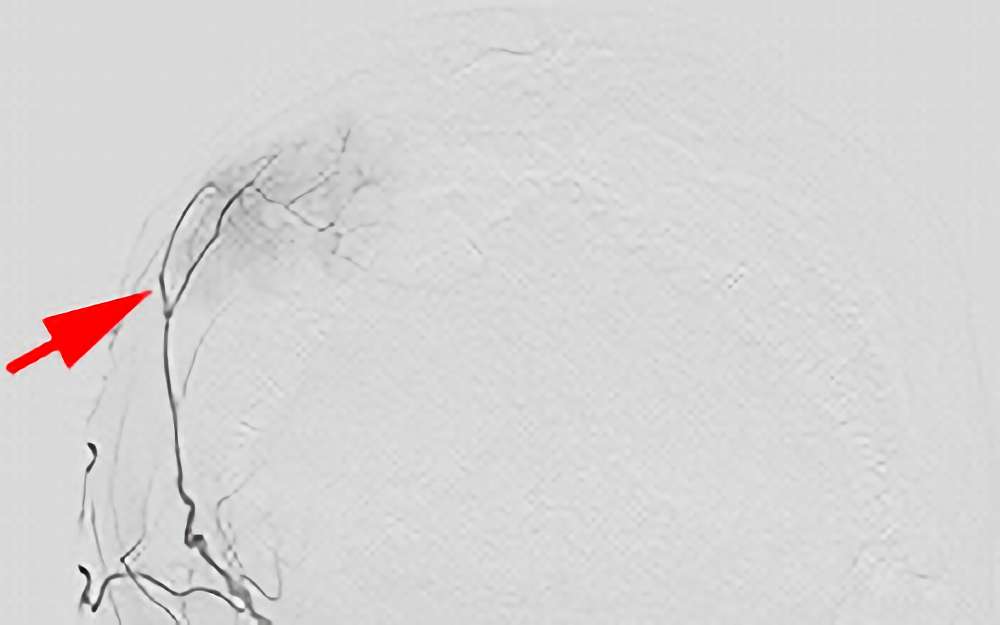

'20年9月2日

円蓋部髄膜腫

50代

大阪府の病院